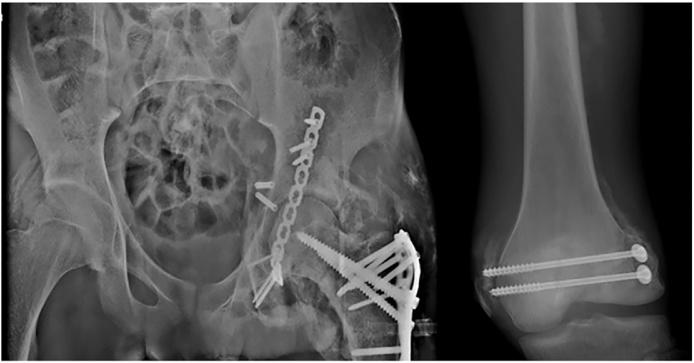

In this case report, we present a 20year old polytraumatized patient with traumatic hip dislocation associated with ipsilateral acetabulum fracture and simultaneous fractures of the ipsilateral femur.

在本病例报告中,我们呈现了一名20岁的多发伤患者,其患有创伤性髋关节脱位,合并同侧髋臼骨折及同侧股骨骨折。